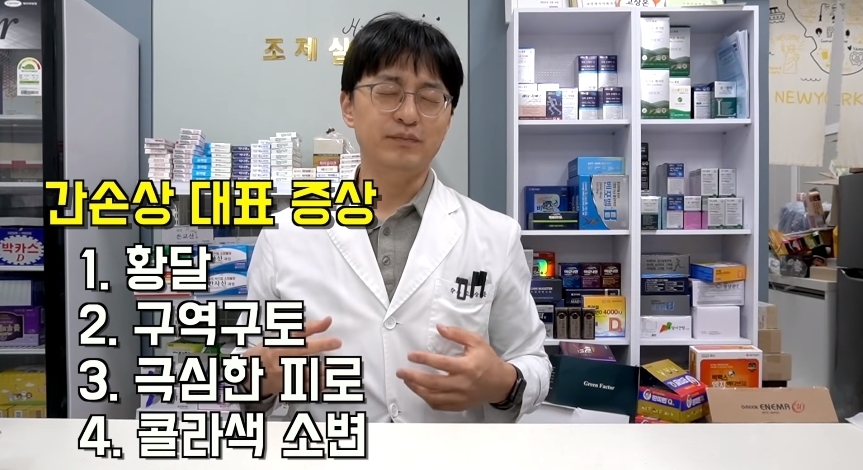

그러나 한번만 먹어도 간이 망가질 수 있다는 영양제들에 대한 글이 온라인 커뮤니티에 올라와 누리꾼들 사이에서 엄청나게 화제가 되고 있다.

해당 게시물에는 먹으면 오히려 몸에 안좋은 영양제들이 올라왔다.